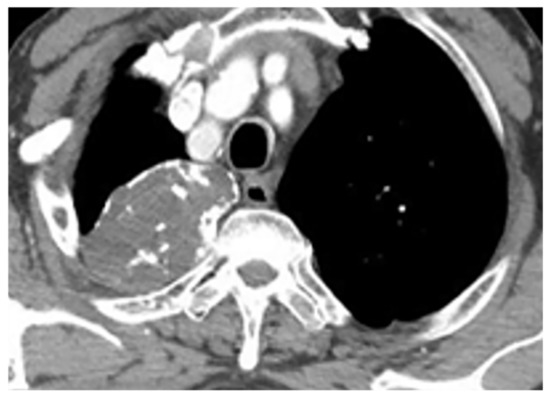

11.3. Mesothelioma

Malignant mesothelioma is the most common primary tumor of the pleura, which is related to prior asbestos exposure with a relatively poor prognosis [56].

Multidetector CT effectively reveals the primary tumoral extension, lymphadenopathy, and extrathoracic metastasis (Figure 27 and Figure 28) [56]. Another CT finding is circumferential pleural thickening (most common finding) with extension along the fissures. Large or punctate osseous or cartilaginous differentiation is more in favor of malignant mesothelioma rather than linear calcification that usually occurs within asbestosis plaques. Dynamic contrast-enhanced computed tomography (DCE CT) enables measuring intratumoral capillary permeability and blood flow, which are beneficial in evaluating treatment response [56,57,58].

Figure 27.

A 67-year-old man with dyspnea and chest pain. Contrast-enhanced CT in axial (a) and coronal (b) planes demonstrate left-sided localized enhancing pleural mass (arrow) with internal areas of necrosis that extend to the posteromedial aspect of the chest wall. Involvement of diaphragmatic pleura and elevation of left hemidiaphragm are also identified.

Figure 28.

A 70-year-old man with dyspnea. The non-contrast CT in the axial plane demonstrates right-sided large pleural effusion, near complete collapse of the right lung (a) after the chest tube insertion; thick circumferential nodular pleural thickening of parietal pleura was shown (arrow) (b). Contrast-enhanced CT of the upper abdomen shows the extension of mesothelioma through the abdominal cavity and wall with indentation over adjacent liver parenchyma (arrow) (c).

MR imaging and 18F-FDG PET/CT are useful in further evaluation of chest wall, diaphragm, and mediastinal invasion [56,57,58,59]. Malignant mesothelioma appears as unilateral hyperintense pleural effusion and pleural thickening with iso to slight hyperintensity to chest wall muscles on T1-weighted and moderate hyperintensity on T2-weighted images. Post-contrast enhancement is expected (Table 3). It is believed that higher metabolic activity on 18F-FDG PET/CT is associated with poor prognosis and shorter survival time [25,56,57,58].